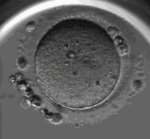

试管婴儿技术的三代胚胎指的是通过不同代际人类卵子和精子的结合,得到的第三代试管婴儿。在芜湖生殖中心,医生们首先从一位年轻女性身上取出卵子,然后将其与一名男性捐献者提供的精子结合。而这位男性捐助者是该家庭亲属之一,因此这个传承了基因的胚胎可以被称为“三代”。最终,在多次培养和筛选后,成功取出了健康胚胎,并且控制了男女比例。